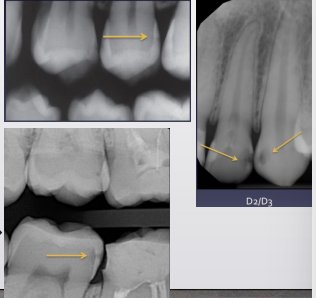

classify this lesion according to the ADA and ICDAS/ICCMS systems

caries within the outer half of the enamel: RA1, E1

classify this lesion according to the ADA and ICDAS/ICCMS systems

caries within the inner half of the enamel: RA1, E1

classify this lesion according to the ADA and ICDAS/ICCMS systems

caries within the outer 1/3 of the dentin: RA3, D1

classify this lesion according to the ADA and ICDAS/ICCMS systems

caries within the middle 1/3 of dentin: RB4, D2

classify this lesion according to the ADA and ICDAS/ICCMS systems

caries within the inner 1/3 of the dentin: RC5, D3

classify this lesion according to the ADA and ICDAS/ICCMS systems

caries in contact w pulp: RC6, D3

top arrow, classify this lesion based on the ADA caries classification system

D1

bottom arrow, classify this lesion based on the ADA caries classification system

D2

classify this lesion based on the ADA caries classification system

D3